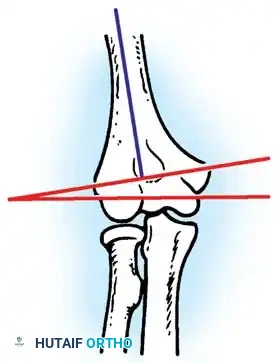

Furthermore, Allende and Freytes identified a pathognomonic radiographic and anatomical feature known as the "radial humeral horn," which was present in 100% of their 35 reported cases.

Fig. 58-23 Anteroposterior radiograph showing lateral dislocation and the characteristic horn of ossification. (From Bruce C, Laing P, Dorgan J, et al: Unreduced dislocation of the elbow: case report and review of the literature, J Trauma 35:962, 1993.)

This "horn" is the direct result of the ossification of a fracture hematoma trapped between the stripped periosteum and the joint capsule near the radial head. Recognizing this structure preoperatively is critical, as it must be surgically excised to achieve concentric reduction.